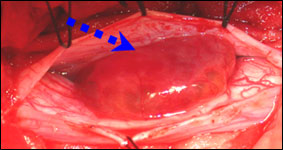

术中见肿瘤位于脊髓腹侧偏左,和颈8神经根关系密切,肿瘤有囊性变,血运中,分块全切肿瘤。